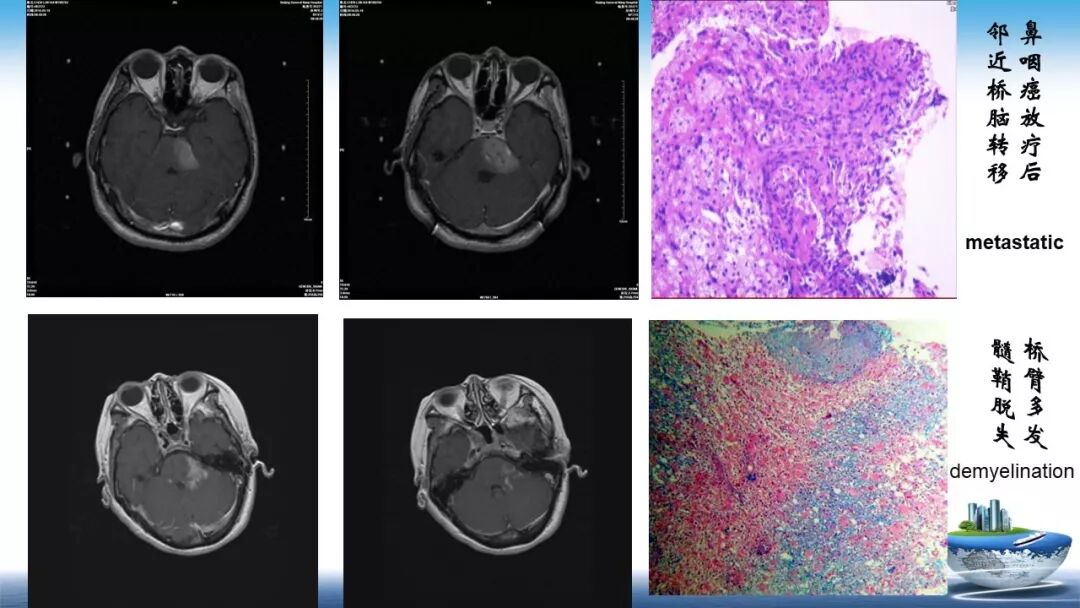

立体定向活检在脑干中线病变精准诊断中的作用

今天为大家带来的是中国人民解放军总医院第六医学中心(原中国人民解放军海军总医院)王亚明、于新、张剑宁带来的精彩课题分享:立体定向活检在脑干中线病变精准诊断中的作用,欢迎观看、阅读!